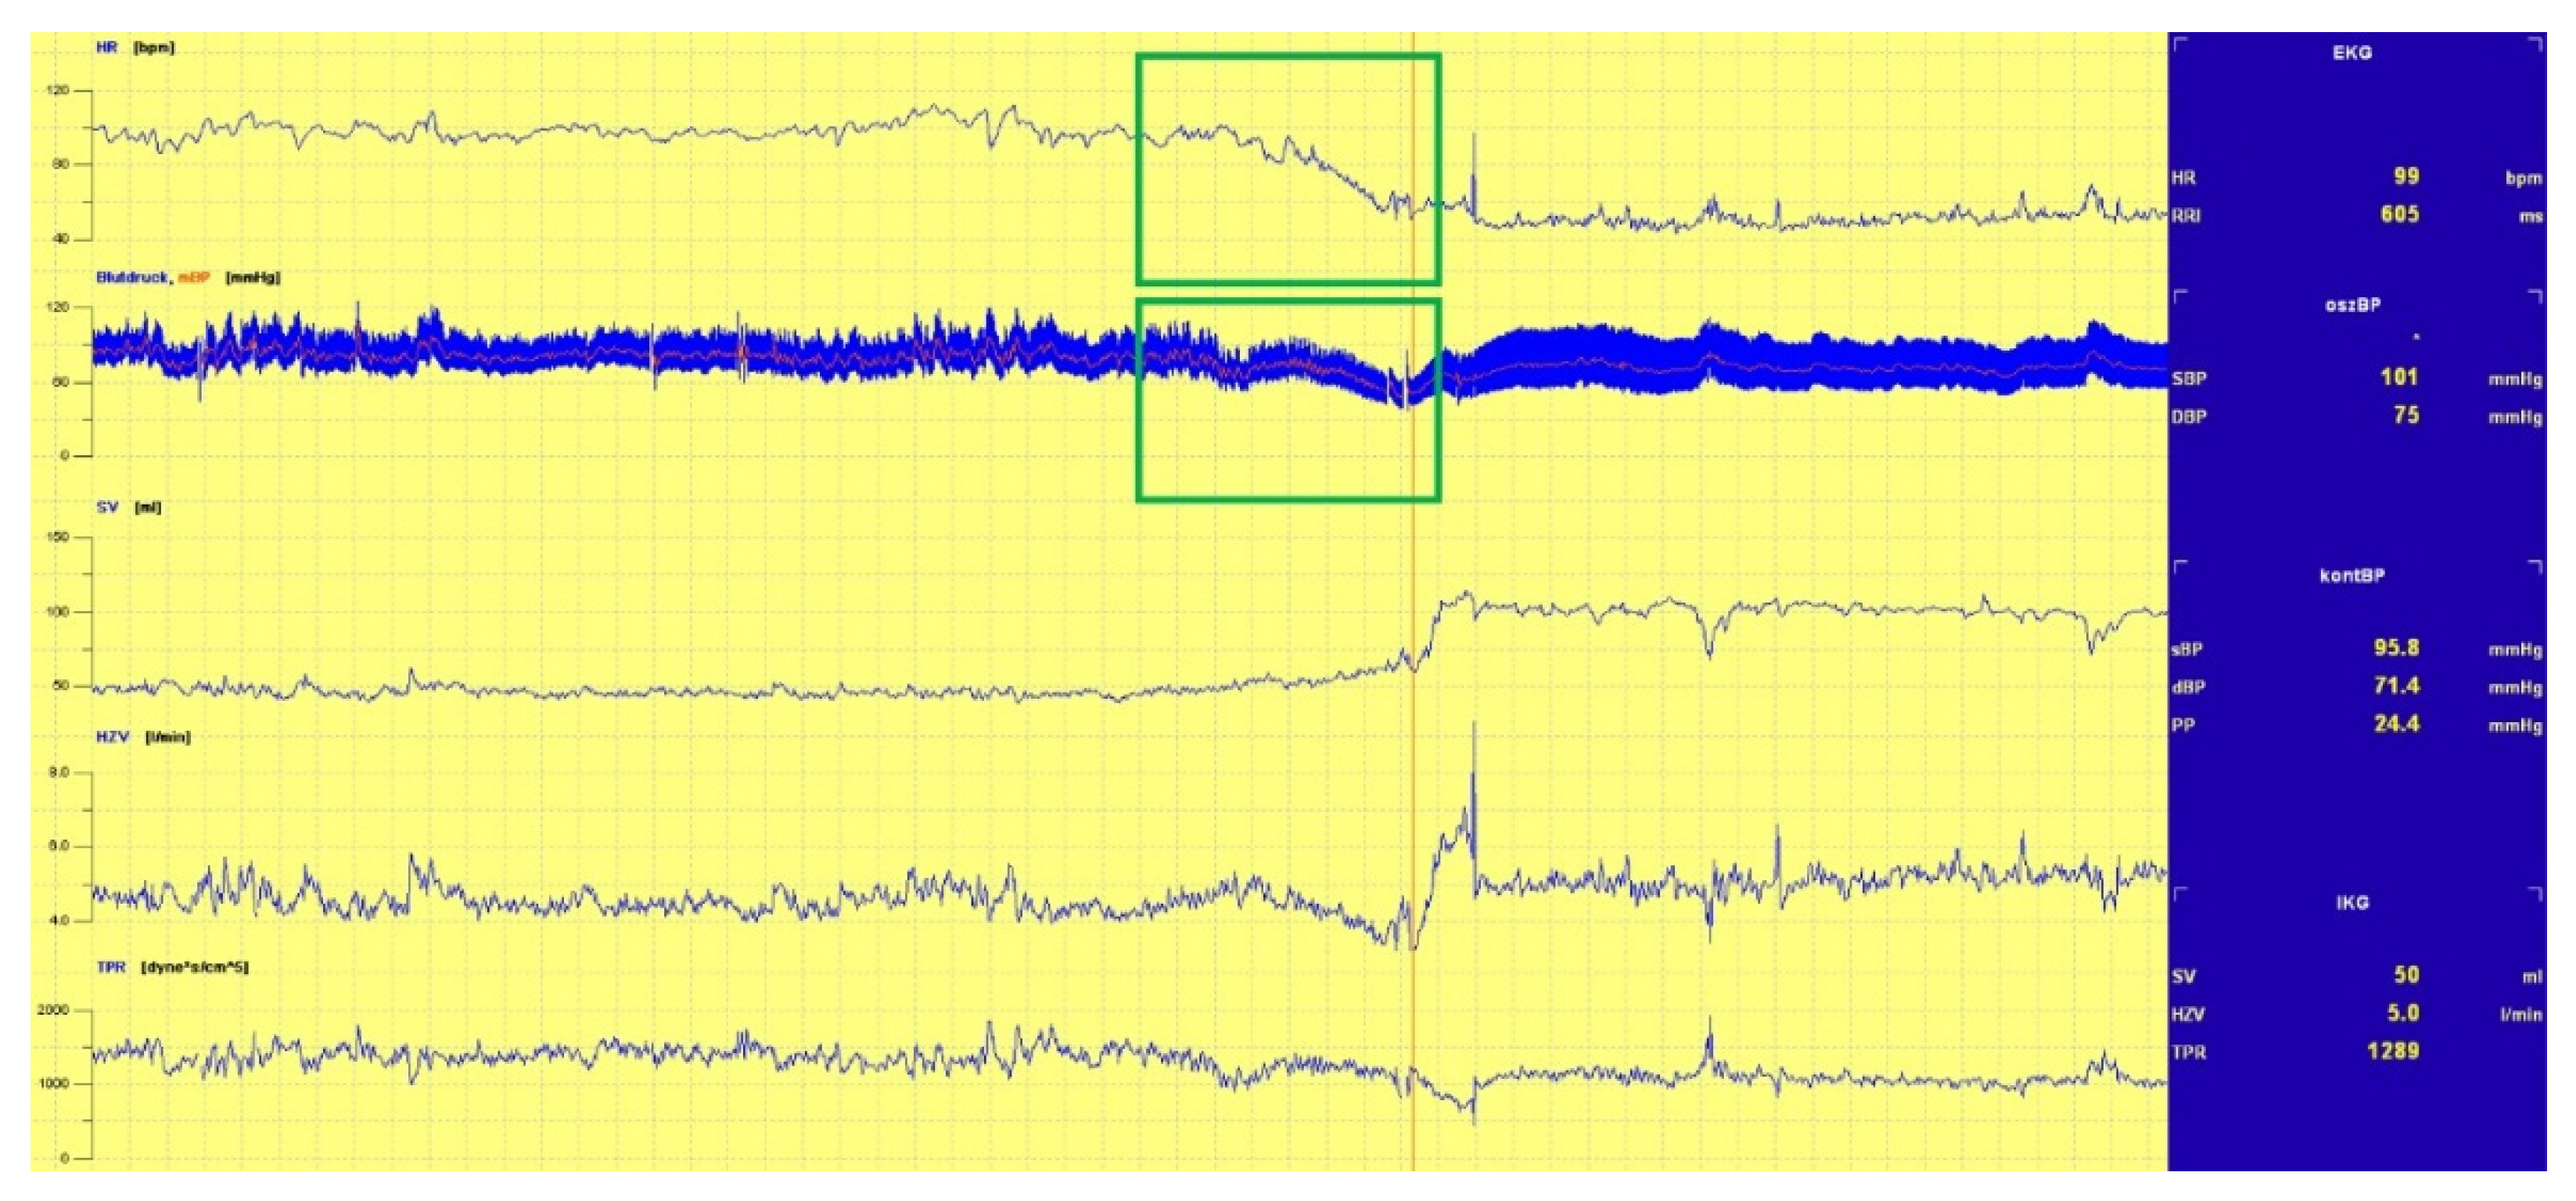

3.1.1. Head-Up Tilt (HUT) Test